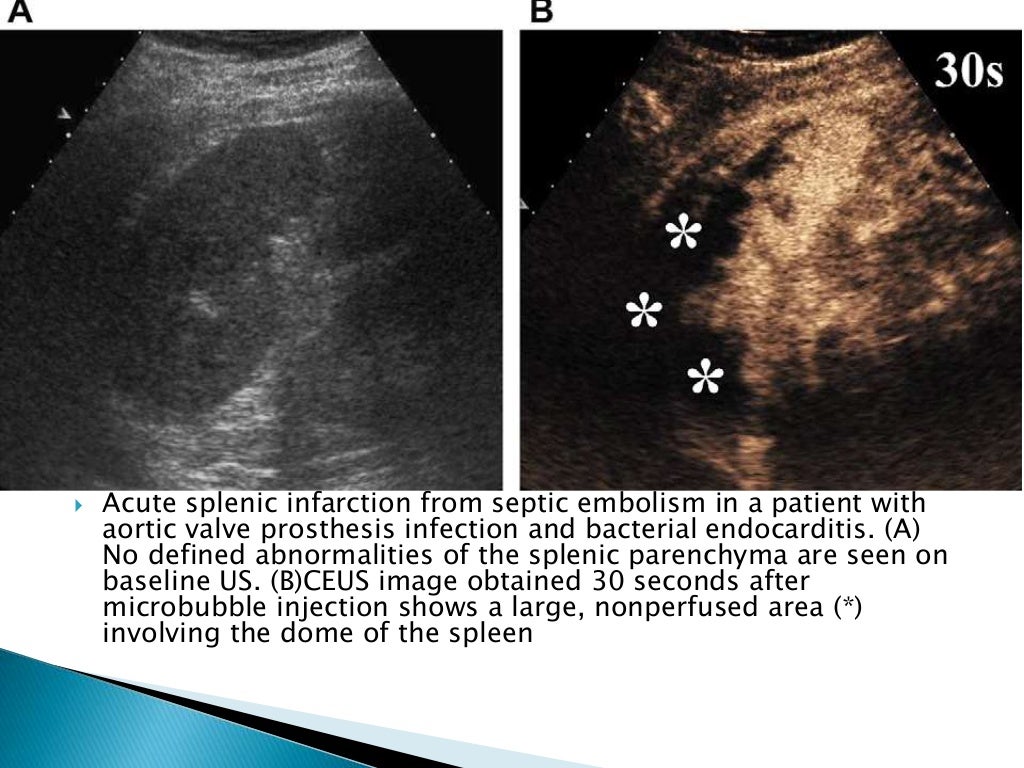

from www.ajronline.org

Untargeted (used in the clinic today) and targeted (under preclinical development). The contrast agent microbubbles reached by an ultrasound beam powerful enough explode producing a strong and very short backscatter. Many scanners have a contrast mode, which utilises a pulse inversion or pulse modulation technique or sometimes a.